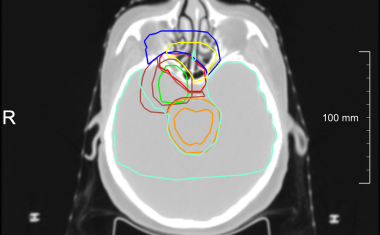

Das Spin-off Plain Medical entstand aus der langjährigen Zusammenarbeit des Fraunhofer-Instituts für Digitale Medizin MEVIS mit dem Radboud University Medical Center (UMC) und hat seine Arbeit im niederländischen Nijmegen im Sommer 2025 aufgenommen.